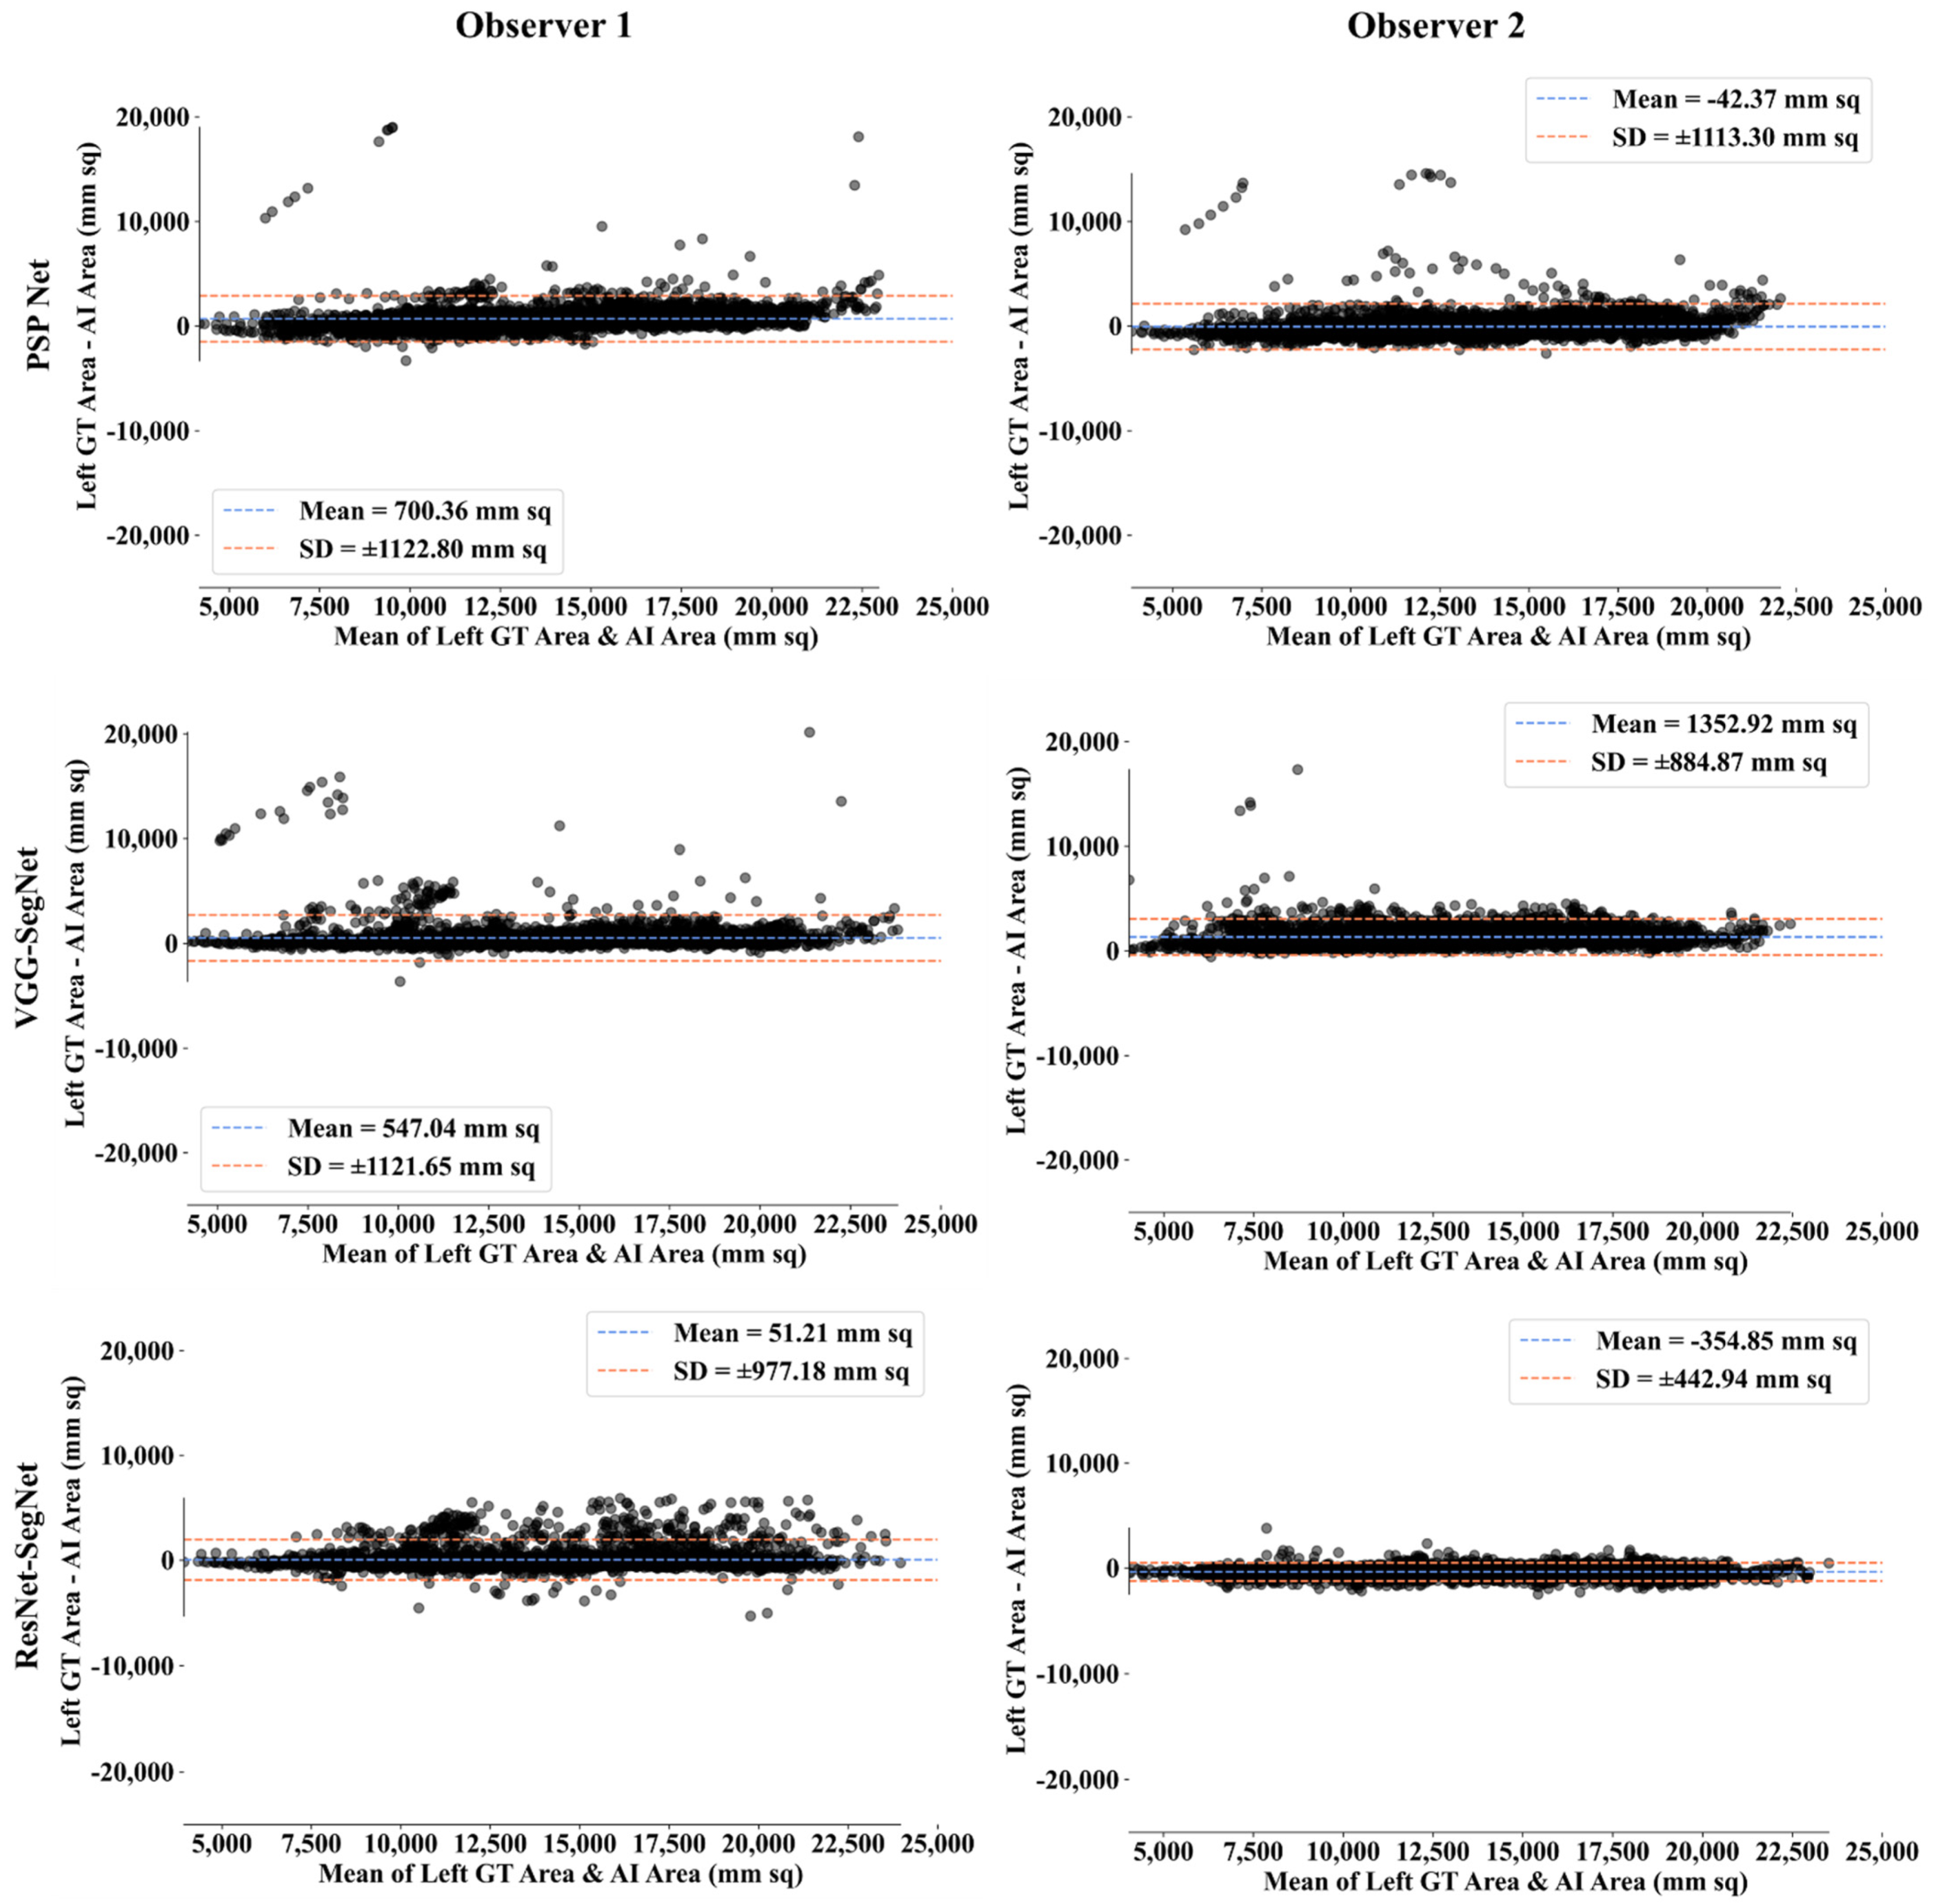

Bland-Altman Plot for Lung Area